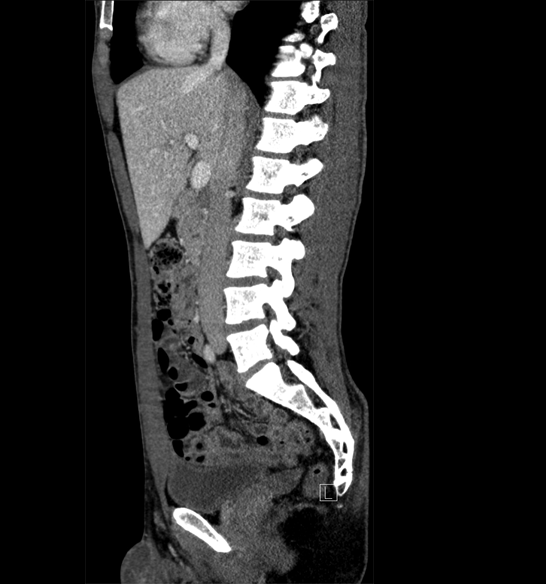

Body

Covers abdominal CT anatomy.